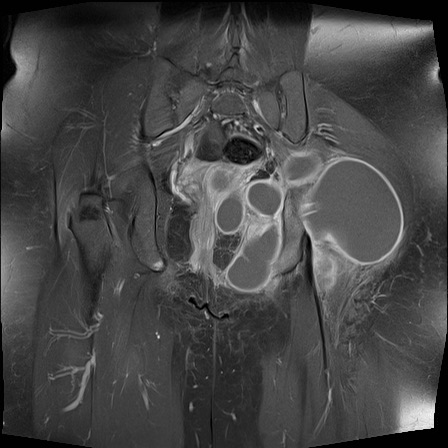

Hình ảnh X-quang khung chậu của bệnh nhân viêm khớp do lao tại khớp háng trái.

Có hẹp khe khớp kín đáo kèm theo xơ cứng dưới sụn tại khớp háng trái.

Các dấu hiệu X-quang này không đặc hiệu và rất có thể là biểu hiện của thoái hóa khớp.

Tiếp tục xem hình ảnh MRI…

Điều bất ngờ với tất cả mọi người là có nhiều ổ áp-xe.

Khi hình thành áp-xe lan rộng như vậy trong khi biểu hiện lâm sàng lại tối thiểu, cần luôn nghĩ đến viêm khớp do lao.

Chẩn đoán viêm khớp do lao được xác lập bằng chọc hút dịch khớp.